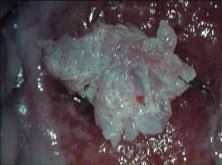

Полипы шейки матки чаще возникают в канале, реже - во влагалищной части, образованы призматическим слизеобразующим эпителием. Полип цервикального канала шейки матки может быть различным по консистенции (мягкий или плотный), окраске (бледно-розовый, белесый, ярко-красный или багровый при кровоизлиянии и воспалении). Поверхность полипа может быть гладкая или неровная в зависимости от преобладания железистого или фиброзного (соединительнотканного) компонента. Причины появления полипов изучены недостаточно. Наиболее часто они встречаются у женщин старше 40 лет. Характерных клинических проявлений полипов нет. Жалобы на патологические выделения из половых путей, в том числе сукровичные, как правило, возникают при развитии вторичных изменений в полипе, например, при воспалительном процессе при травмировании полипа и последующем его инфицировании или при расстройстве кровообращения. Достаточно часто в полипах цервикального канала развивается плоскоклеточная метаплазия. У беременных соединительнотканная основа полипа может изменяться по типу децидуальных преобразований слизистой полости матки с образованием децидуального полипа.

Рис.1 Полип шейки матки (макропрепарат)